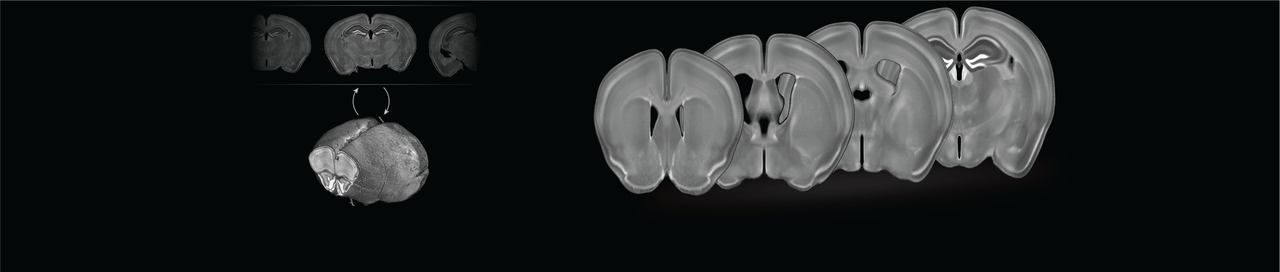

We collected consecutive coronal slices from 12 mice (C57BL/6) covering the majority of the cerebrum and DAPI-stained them. With the help of Allen Mouse Brain Common Coordinate Framework (CCFv3) we were able to reconstruct all 12 brains. This was done by iteratively stacking the 2-dimensional slices into 3-dimensional volumes, registering, and slicing. With the reconstructed brains, we could perform the template creation in 3-dimensional space. Using this new template in combination with the CCFv3 we started over with the reconstruction and template creation resulting in the final well-defined DAPI template (shown in the beginning of the post).

We were thrilled with how well the reconstruction process worked and happy to see a well-defined and smooth template. New coronal slices were easily registered to the template, so we wrote a small python program for automatic template-based segmentation (see the full paper for examples). To encourage the scientific community to utilize and improve the template, we have made all the data available in a well-structured and ordered fashion here: https://doi.org/10.12751/g-node.16wrxa